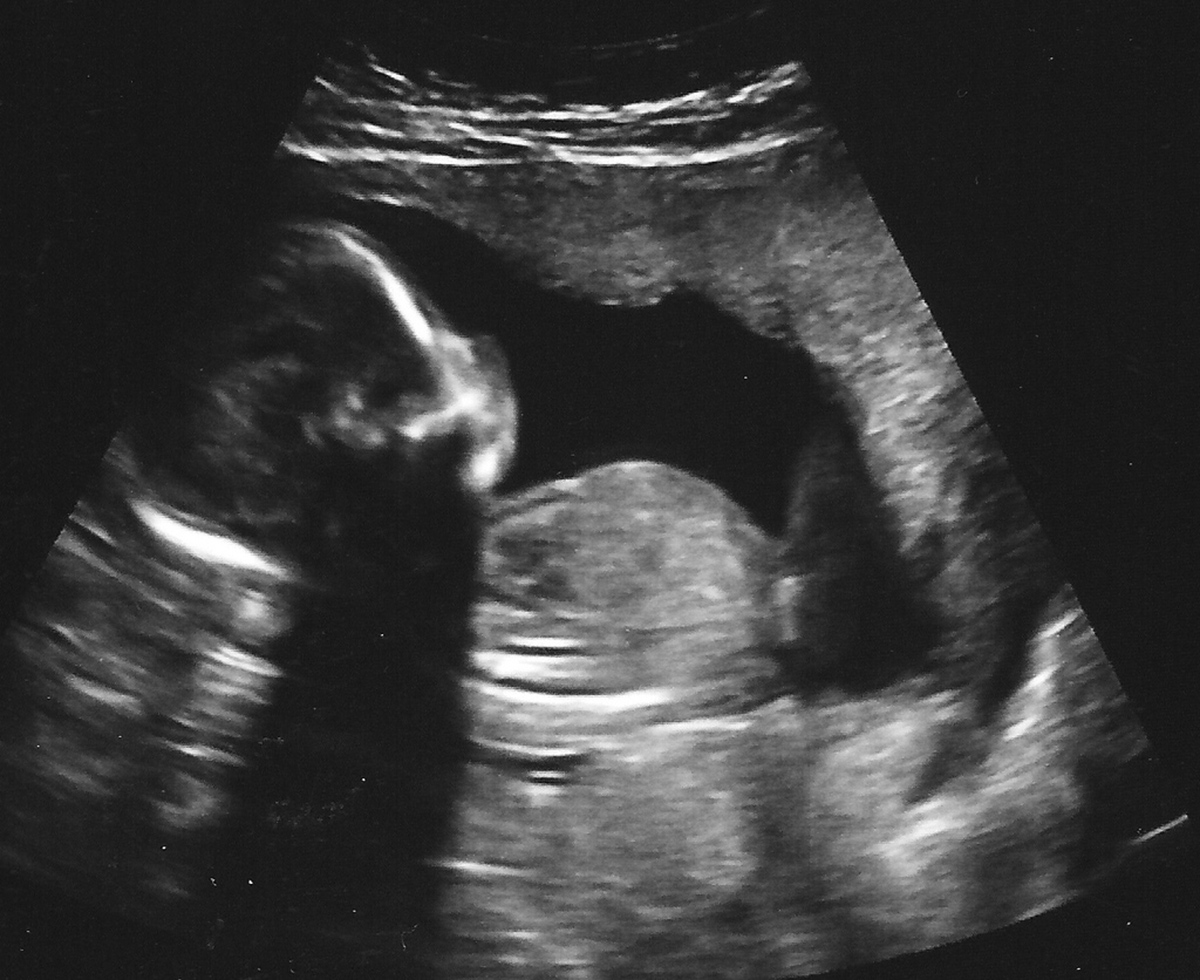

Ultrasound during pregnancy have become so common now, that practically every woman will have at least one, and most likely several, over the course of her pregnancy. Depending on the type of healthcare provider you have chosen for your prenatal care, you might have your first ultrasound scheduled during the first trimester, or the beginning of the second trimester. Most expecting moms agree ultrasounds are exciting! For many, they provide the first real chance to bond with their unborn baby. What can you expect from your first ultrasound during pregnancy?

Depending on the length of your pregnancy, an ultrasound examination will look into various things. First, the ultrasound will confirm that your baby's heartbeat is in order, and that your baby is developing properly. You will see and hear your baby's heart beat for the first time! The technician will look whether all internal organs are present and that there are no anomalies. They will also look whether the head and body have the same gestational age, for instance. An early ultrasound can be used fairly accurately to determine the length of your pregnancy. If you had irregular periods before getting pregnant, and do not know exactly when you conceived, this can be useful in telling the doctor when you are "due".

The father you are along in pregnancy, the less accurate ultrasound becomes as a method of determining gestational length. If you do know when you conceived, and your baby is a little bit behind or in front, there is no reason to be worried for those of us who have had several ultrasounds in any one pregnancy, this must have happened at least once. Babies grow at different rates, inside the uterus as well as on the outside!

Then, there is the part of the ultrasound that is most exciting to most of us perhaps, the ultrasound technician will be able to tell your baby's gender! Gender can be seen as early as 14 weeks into your pregnancy, but only if the baby's position is favorable, meaning that the tech will have access to the right spots. Don't be disappointed if you don't find out the sex of your baby at the first ultrasound. You'll probably go on to have another one.

Finally, ultrasounds later in pregnancy can determine the location of the placenta, which can be very important. Placenta previa, a condition in which the placenta attached over the opening of your cervix, is a serious condition that requires a c-section, because your baby will not be able to exit the uterus naturally.